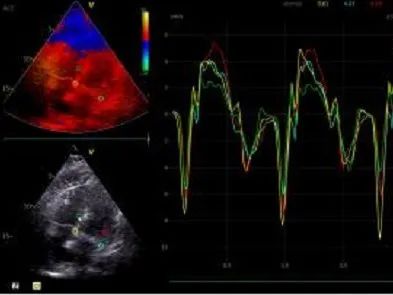

超声检查

• 左心房稍大;

• 升主动脉增宽;

• 室间隔与左室壁稍厚;

• 主动脉瓣重度狭窄并轻度反流;

• 二尖瓣轻微反流;

• 左室充盈功能减弱;

• 左心室舒张末期内径:42mm;

• 左心室收缩末期内径:23mm;

• 主动脉瓣口流苏峰值:412cm/s;

• 主动脉瓣跨瓣压差:60mmHg。

术后超声显示:释放后瓣膜位置形态良好,瓣叶活动可,患者的跨瓣压差由术前的60mm/Hg改善至术后的6mm/Hg,术后患者血流动力学得到明显改善,获益明显。